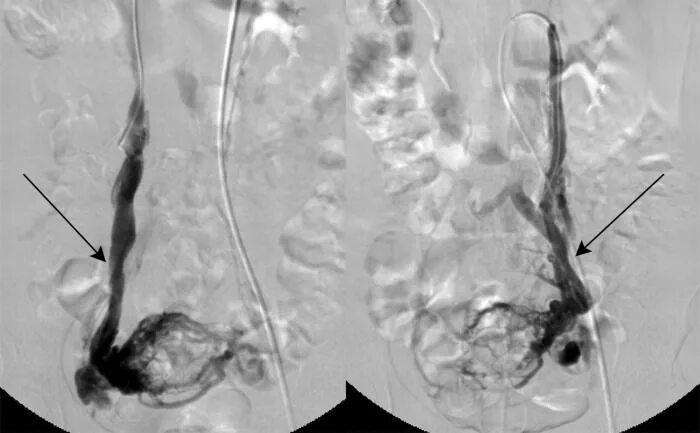

Варикоз малого таза симптомы лечение